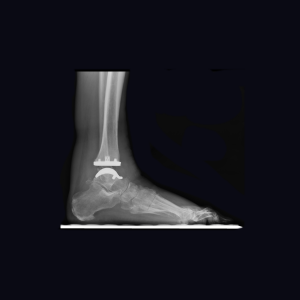

Follow-up is too short at this point to report outcomes for the Vantage. However, my colleagues and I have been collecting data on every Vantage that we implant, including validated patient-reported outcomes, accepted objective outcomes measures and standardized radiographic evaluations. (Fig 10 A and B) To date, our observations reflect high patient satisfaction, low complication rates and a trend toward favorable range of motion confirmed with objective postoperative radiographic dorsiflexion and plantarflexion measurements. While my colleagues and I initially limited the Vantage to end-stage ankle arthritis with minimal deformity, more recently we expanded indications to include varus and valgus ankle arthritis. At early follow-up our results are equally favorable for end-stage ankle arthritis with and without deformity.